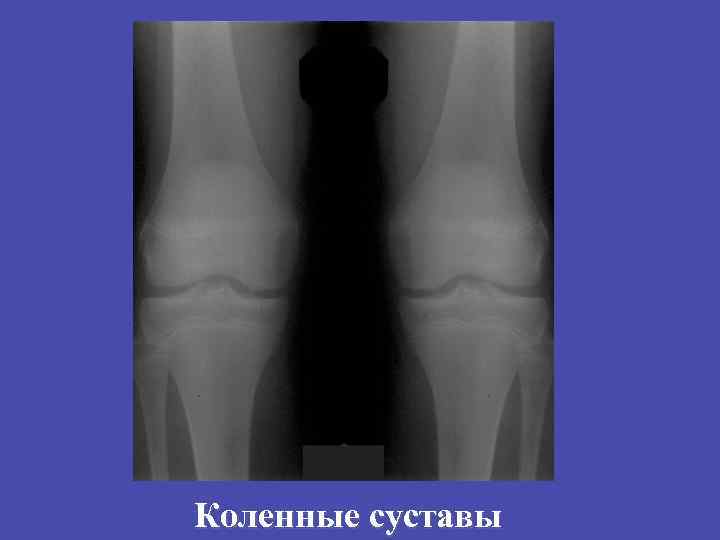

Коленные суставы

Туберкулезный гонит, предартритическая фаза 56

Туберкулезный гонит, предартритическая фаза 57